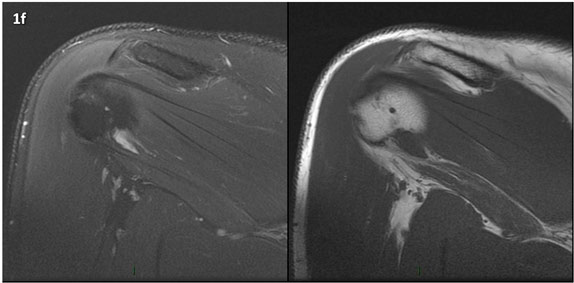

Figura 1 (a-g): Imagens consecutivas de RM no plano coronal nas ponderações DP com supressão de gordura (DP SG) à esquerda e T1 à direita. Clique na seta para passar as imagens.

Figura 1 (a-g)': Imagens consecutivas de RM no plano coronal nas ponderações DP com supressão de gordura (DP SG) à esquerda e T1 à direita mostrando . Clique na seta para passar as imagens.

Figuras 1b’ a 1g’ mostrando atrofia da porção superior do músculo redondo menor (seta salmão), com lipossubstituição mais evidente das mais fibras laterais (seta amarela). As fibras mais inferiores e mediais têm atrofia menos evidente.

Repare que estas alterações não são evidentes nas imagens com supressão de gordura.